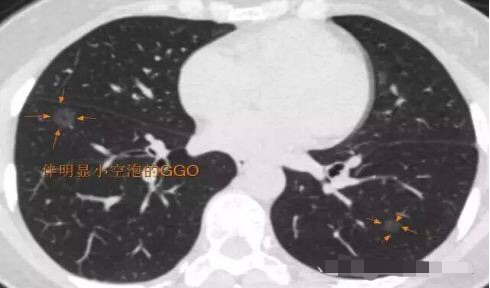

突然出现的磨玻璃结节

薄层CT配合三维重建,以及定期动态CT观察有助于鉴别良恶性GGO:伴有明显分叶、空泡、胸膜凹陷征或明显实性成分(荷包蛋,中间厚,外周薄)的GGO提示恶性病变;随访过程中病灶消散或明显缩小者考虑炎症反应可能;随访过程中,如GGO增大,病灶密度变实,或兼有肿瘤微血管CT成像征时,提示恶性病变。

空泡型GGO